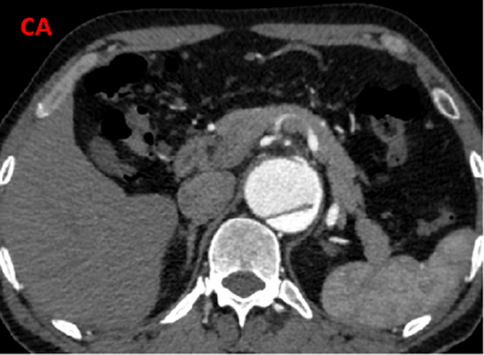

夹层近端封闭良好。夹层动脉瘤累及整个内脏区动脉,腹腔干、肠系膜上动脉假腔供血,腹腔干开口重度狭窄;右肾动脉真假腔供血,以假腔为主;左肾动脉真腔供血。肾下腹主动脉段无裂口,右侧髂外动脉存在裂口。

CT影像